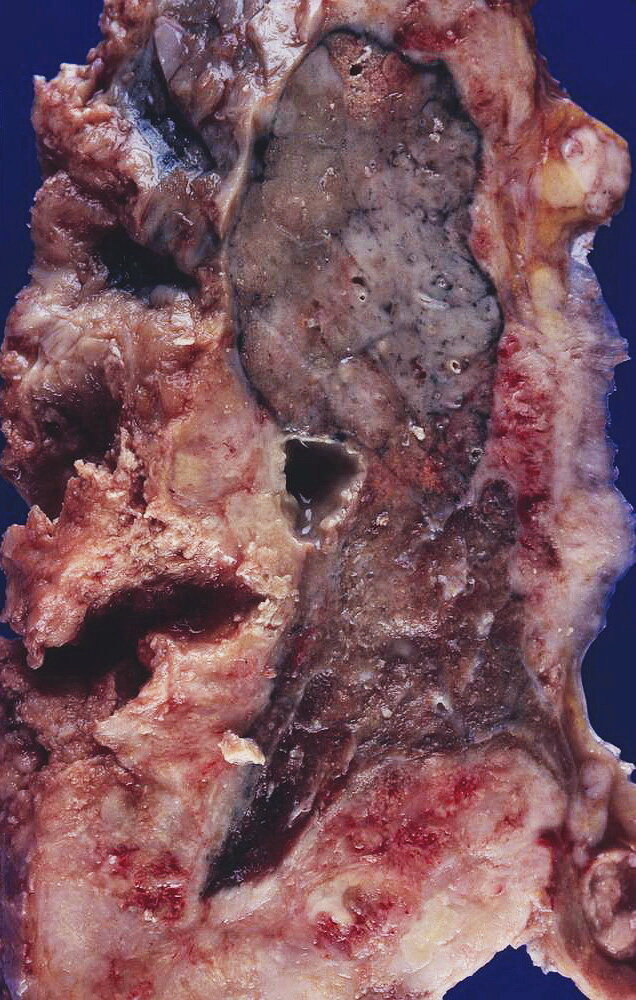

• Biopsy

• Microscopic asbestos bodies

• Fibrosis

Biopsy

• Uses

• Histopathological confirmation and differentiating mesothelioma from adenocarcinoma

• Confirmation of mesothelioma subtype: epithelioid, sarcomatoid, or mixed

• Modality: usually thoracoscopic biopsy (or laparoscopic biopsy: in suspected peritoneal mesothelioma) [10]

• Findings

• Mesothelioma cells (tumor cells with long and slender microvilli, tonofilaments, and desmosomes on electron microscopy) [12]

• Psammoma bodies (rare, not specific for mesothelioma) [12]

• Immunohistochemical markers: calretinin, cytokeratin 5 and 6, thrombomodulin, and mesothelin [9]

Histopathology is required to confirm the diagnosis of mesothelioma.